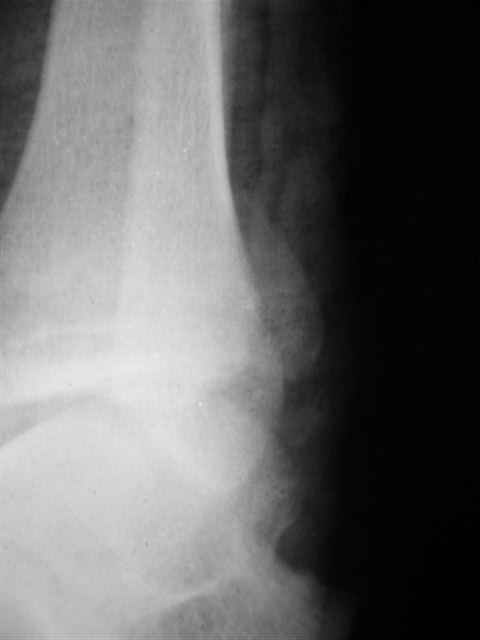

Re: открытый перелом мыщелков бедра, латерального

Отправитель: Evgueny Tschekashkin 19 Декабрь 2004, 23:02

Уважаемый Иван,

Я предупреждал, что ничего сверхъестественного. Каюсь, что одна из спиц прошла несколько дальше, чем нужно было, но главное - перелом стабилизирован и больной работает суставом в полном объёме, несмотря на представленную раннее травму коленного сустава.

Всего вам Доброго,

Евгений И Чекашкин